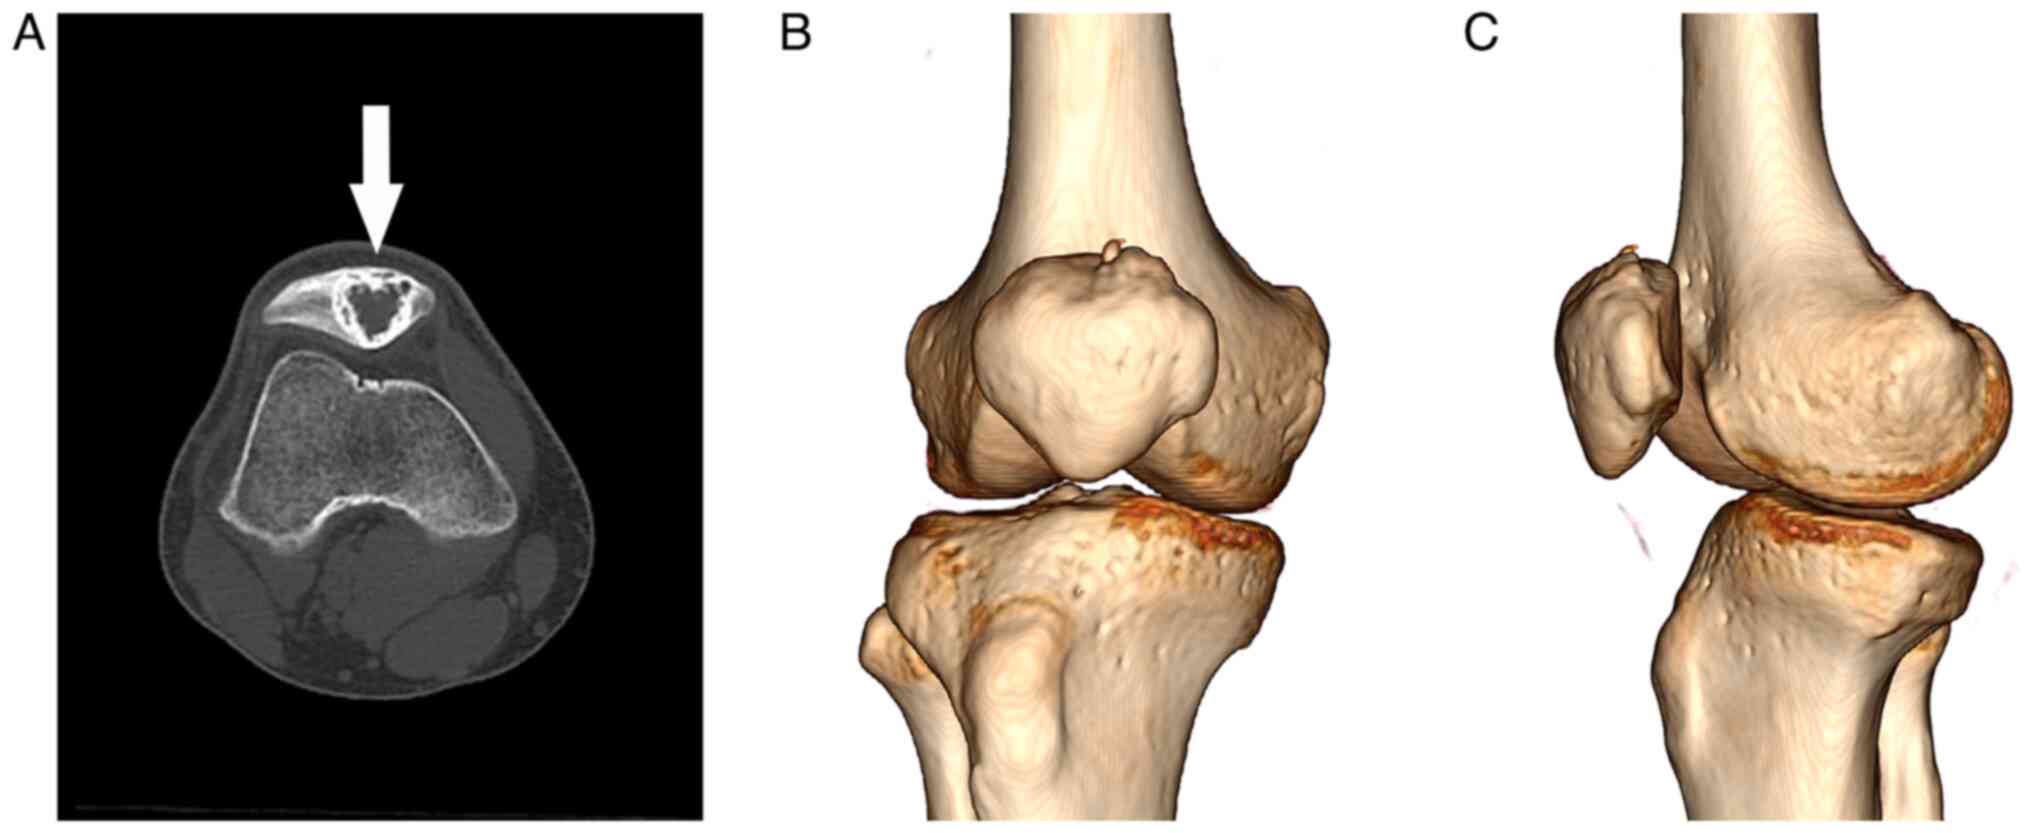

At the last follow-up 2 years postoperatively, no clinical and radiological evidence of local recurrence was noted, and the bone graft was blurred and fused (Fig. 6). The patient's sports and physical functioning domain score was 100 points. In spite of satisfactory outcome, we require a long-term regular follow-up in order to perform an early detection and treatment for a possible recurrence.

Figure 6

X-ray images of the right knee at the 2-year follow-up showing that the bone graft was blurred and fused; there was no radiological evidence of local recurrence. (A) Anteroposterior plane and (B) lateral plane.